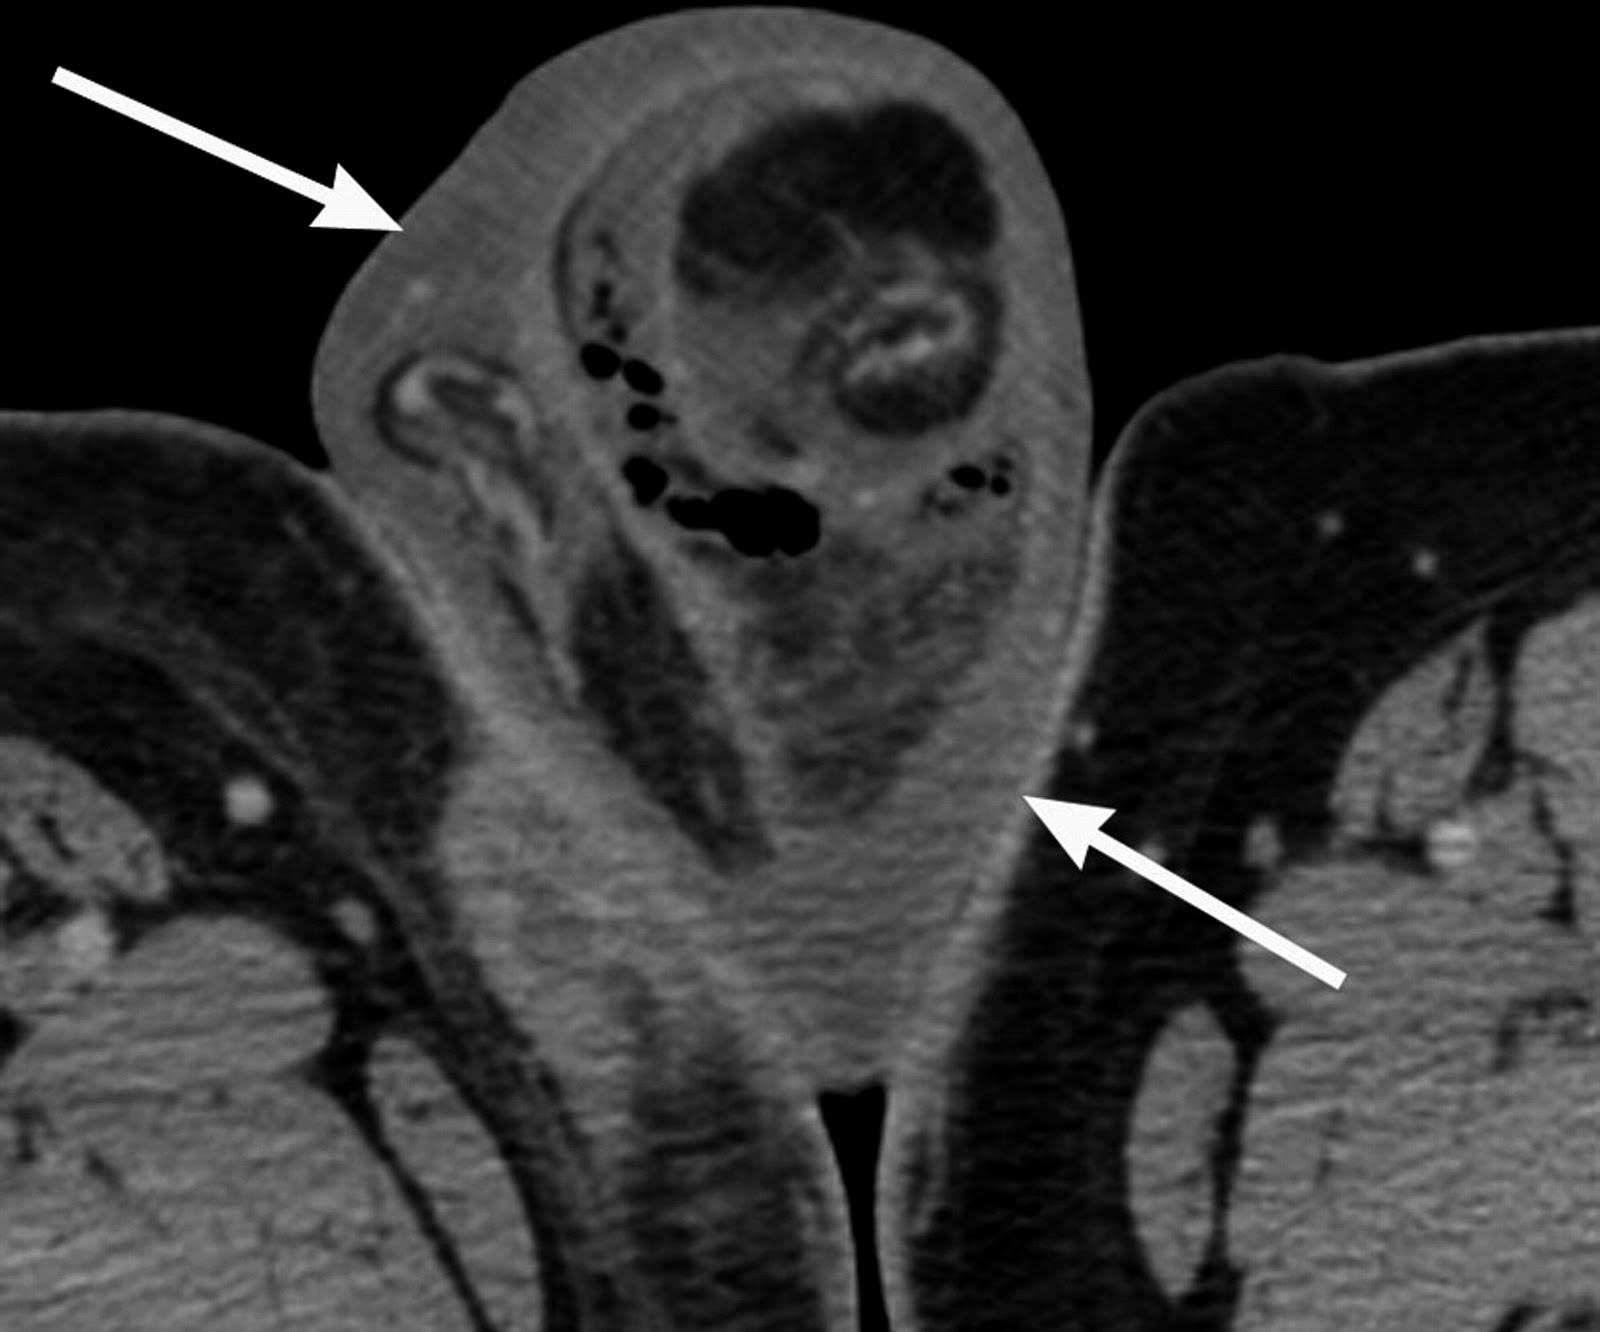

Las radiografías simples pueden revelar la existencia de aire en los tejido blandos, pero no es patognomónico. La ecografía es una herramienta diagnóstica más útil, por su capacidad de diferenciar la gangrena de Fournier de la patología intraescrotal. Ecográficamente, la gangrena de Fournier se manifiesta por la presencia de gas subcutáneo. La realización de un TAC también puede demostrar de una forma muy clara la presencia de gas en tejido celular subcutáneo, llegando al diagnóstico de la enfermedad cuando ésta todavía no se ha manifestado clínicamente en todo su esplendor.